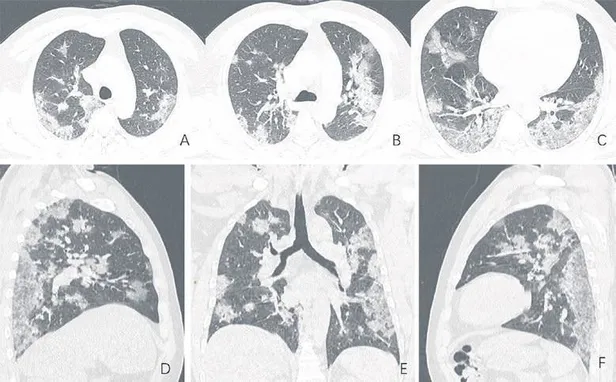

Coronavirüs (COVID-19) hastalarının akciğerlerinde buzlu cam benzeri yapılar tespit edildi

Uzmanlar, iyileşen COVID- 19 hastalarının akciğerinde buzlu cam benzeri yapılar oluştuğunu saptadı. Dr. Owen Tsang Tak-yin, araştırmayla ilgili şu açıklamayı yaptı: Bazı hastalarda akciğer fonksiyonu, iyileşme sonrasında yüzde 20 ila 30 oranında azalabiliyor.